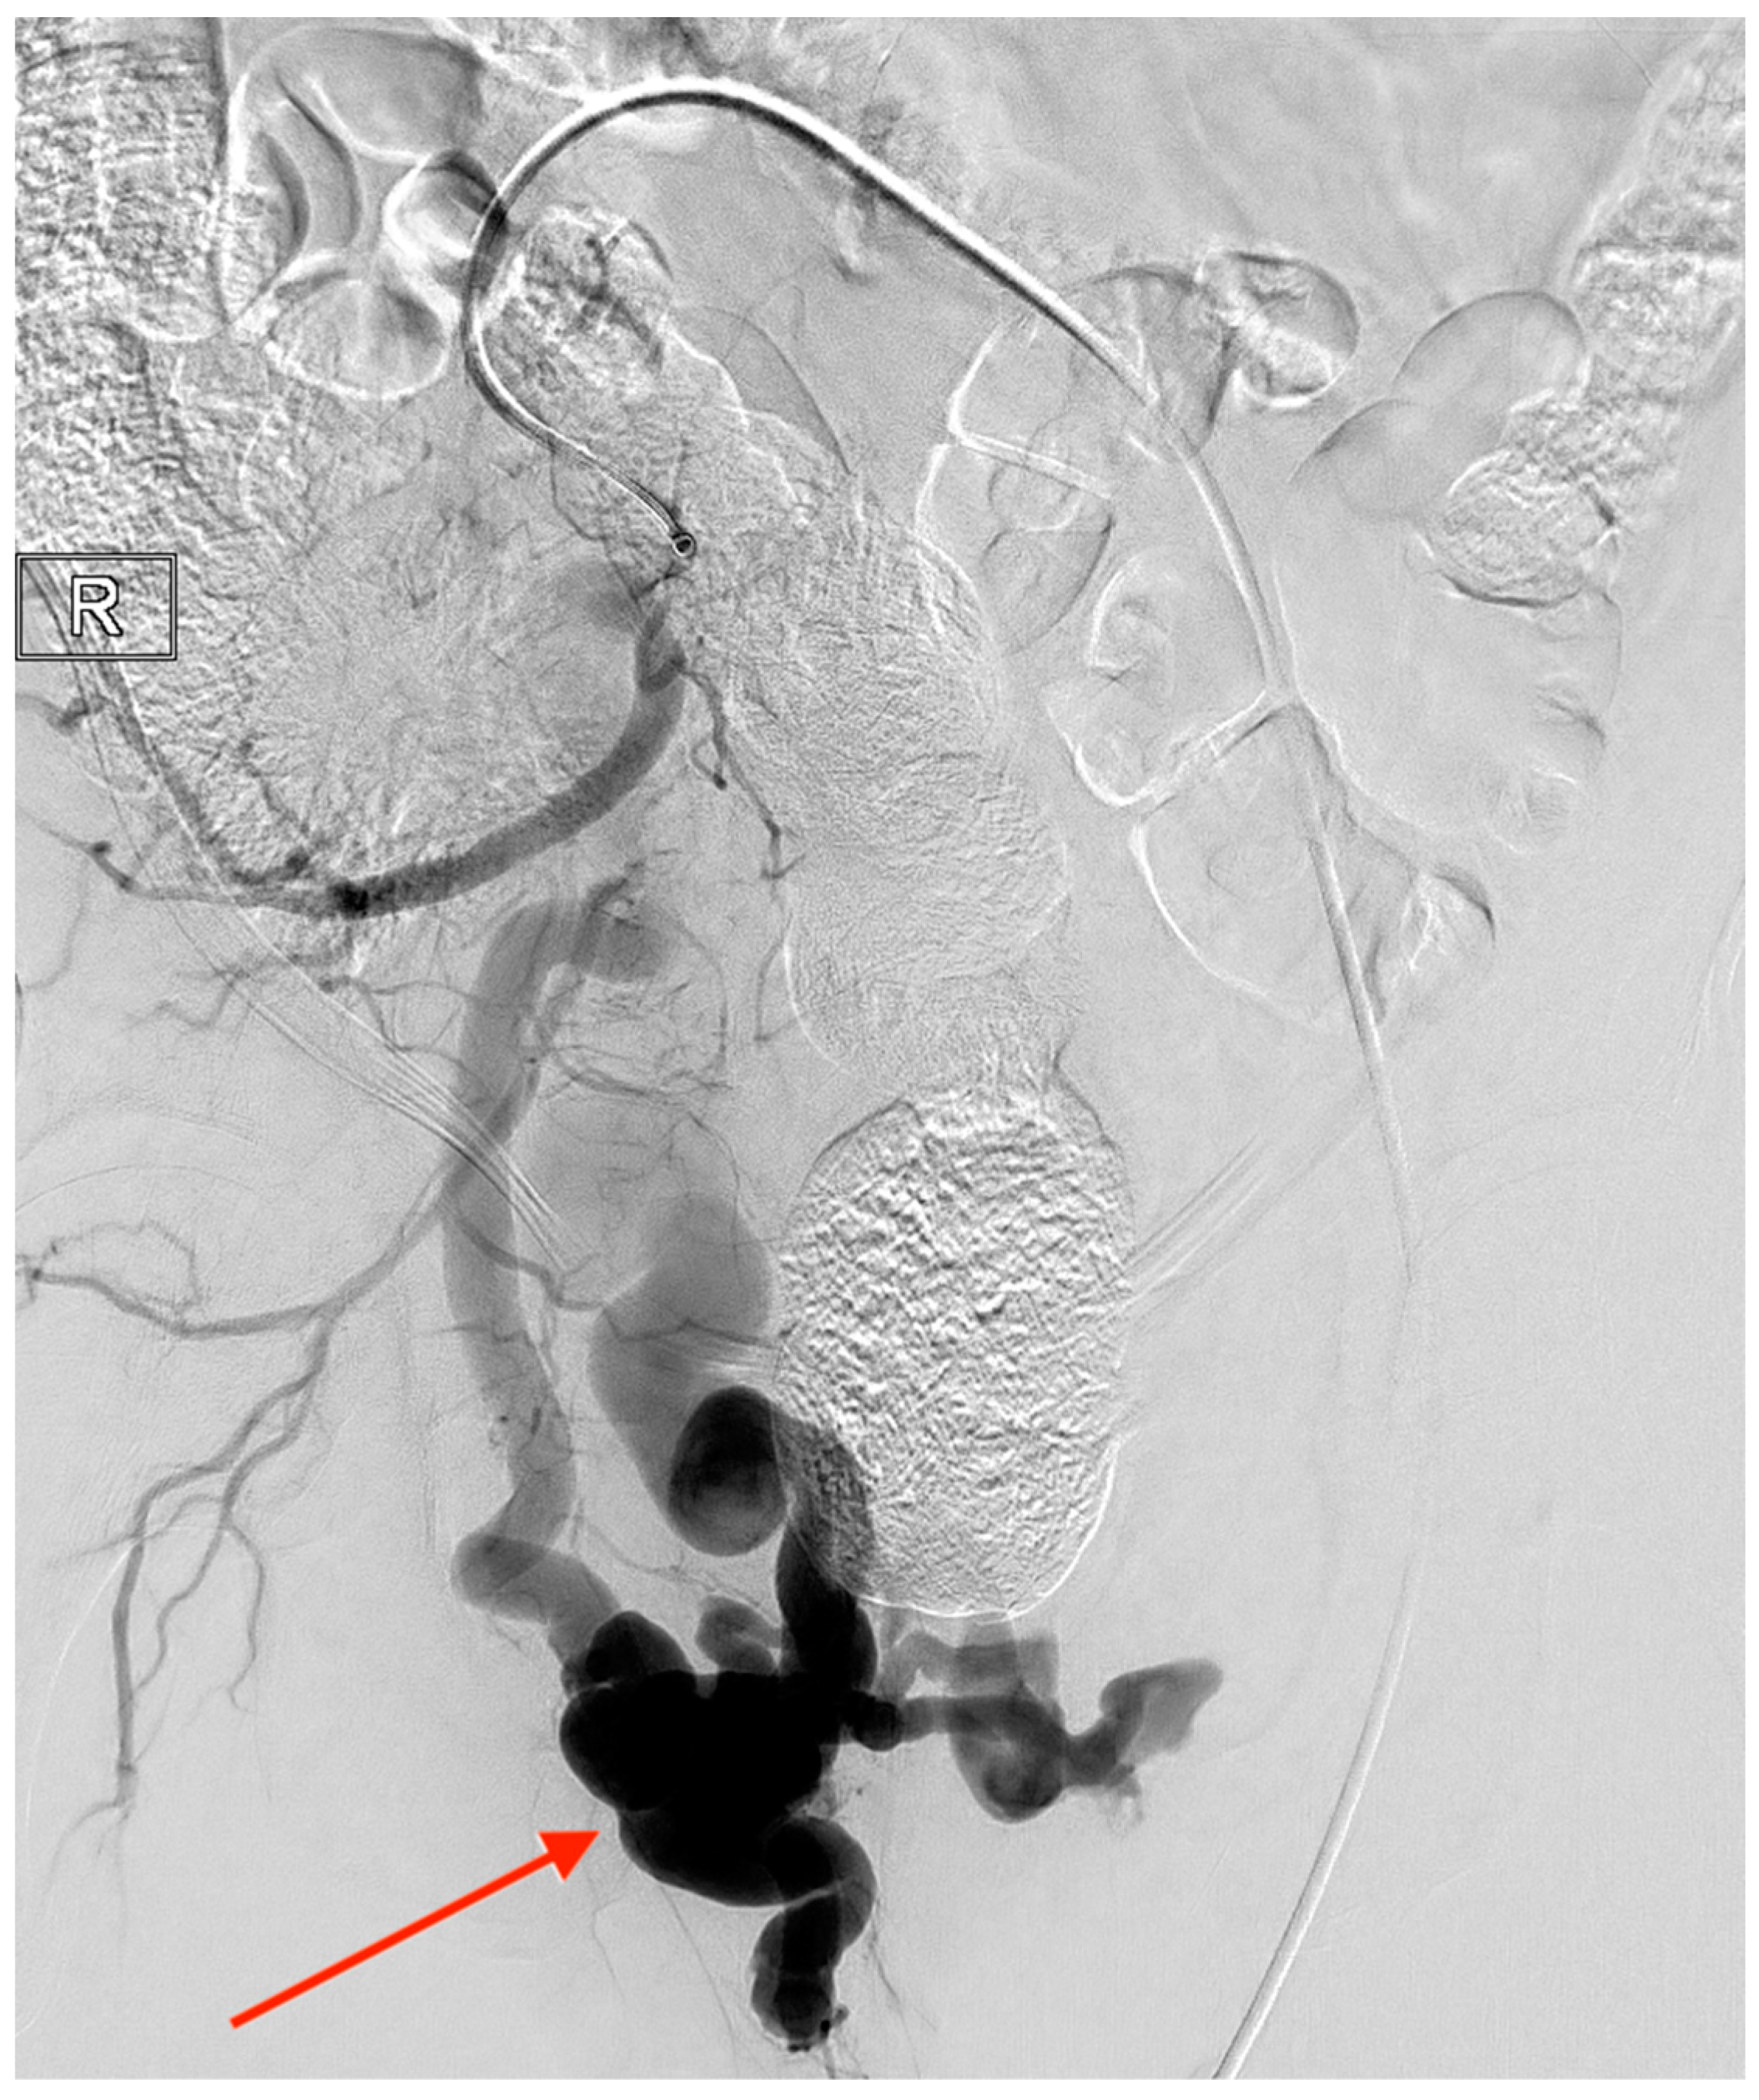

Arteriovenous Malformation of the Prostate Vasculature as a Cause of Torrential Bleeding during Transurethral Resection of the Prostate